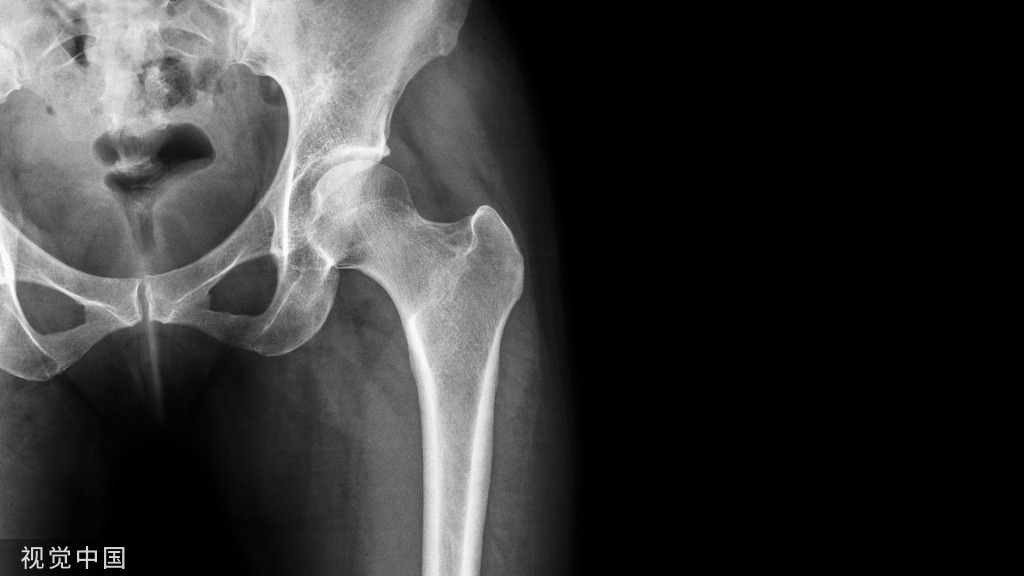

现在对股骨骨折进行牵引时,一般与 Thomas 架整合使用(图 10)。

而牵引远端可采用骨牵引(图 11),或皮牵引(图 12)。

图 11a  胫骨骨牵引

图 11b  跟骨骨牵引